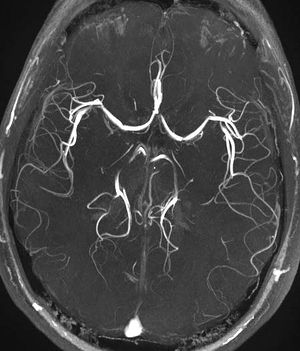

تصوير الأوعية بالرنين المغناطيسي

تصوير الأوعية بالرنين المغناطيسي (MRA)، هي مجموعة من التقنيات تستخدم التصوير بالرنين المغناطيسي لتصوير الأوعية الدموعية. ويستخدم تصوير الأوعية بالرنين المغناطيسي للحصول على صور للشرايين in order to evaluate them for stenosis (abnormal narrowing), occlusion or aneurysms (vessel wall dilatations, at risk of rupture). MRA is often used to evaluate the arteries of the neck and brain, the thoracic and abdominal aorta, the renal arteries, and the legs (called a "run-off").

- Time-of-flight (TOF) or Inflow angiography, uses a short echo time and flow compensation to make flowing blood much brighter than stationary tissue. As flowing blood enters the area being imaged it has seen a limited number of excitation pulses so it is not saturated, this gives it a much higher signal than the saturated stationary tissue. As this method is dependent on flowing blood, areas with slow flow (such as large aneurysms) or flow that is in plane of the image may not be well visualized. This is most commonly used in the head and neck and gives detailed high resolution images.

Occasionally, MRA directly produces (thick) slices that contain the entire vessel of interest. More commonly, however, the acquisition results in a stack of slices representing a 3D volume in the body. To display this 3D dataset on a 2D device such as a computer monitor, some rendering method has to be used. The most common method is Maximum intensity projection (MIP), where the computer simulates rays through the volume and selects the highest value for display on the screen. The resulting images resemble conventional catheter angiography images. If several such projections are combined into a cine loop or QuickTime VR object, the depth impression is improved, and the observer can get a good perception of 3D structure. An alternative to MIP is direct volume rendering where the MR signal is translated to properties like brightness, opacity and color and then used in an optical model.

MRA has been successful in studying many arteries in the body, including cerebral and other vessels in the head and neck, the aorta and its major branches in the thorax and abdomen, the renal arteries, and the arteries in the lower limbs. For the coronary arteries, however, MRA has been less successful than CT angiography or invasive catheter angiography. Most often, the underlying disease is atherosclerosis, but medical conditions like aneurysms or abnormal vascular anatomy can also be diagnosed.